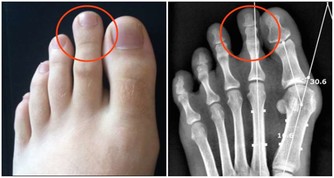

1932年的一項研究結果得出,改變飲食有助於改善蛀牙問題。研究人員得出結論,缺乏礦物質和脂溶性維生素以及過度攝取植酸與加工糖較易引起蛀牙。

根據《Remedy Daily》網站的報導,作家David Wolfe先生利用了1932年的研究,想出了以下5個有助於治療蛀牙的方法,一起來看看吧!

礦物質是對抗蛀牙的關鍵。當牙齒琺瑯質變弱,就失去礦物質的含量。補充流失礦物質的最好辦法(除了食用富含礦物質的食物以外)就是使用礦化牙膏。這就是為什麼許多市售的牙膏都含有氟的成分,它能夠促進牙齒琺瑯的健康。